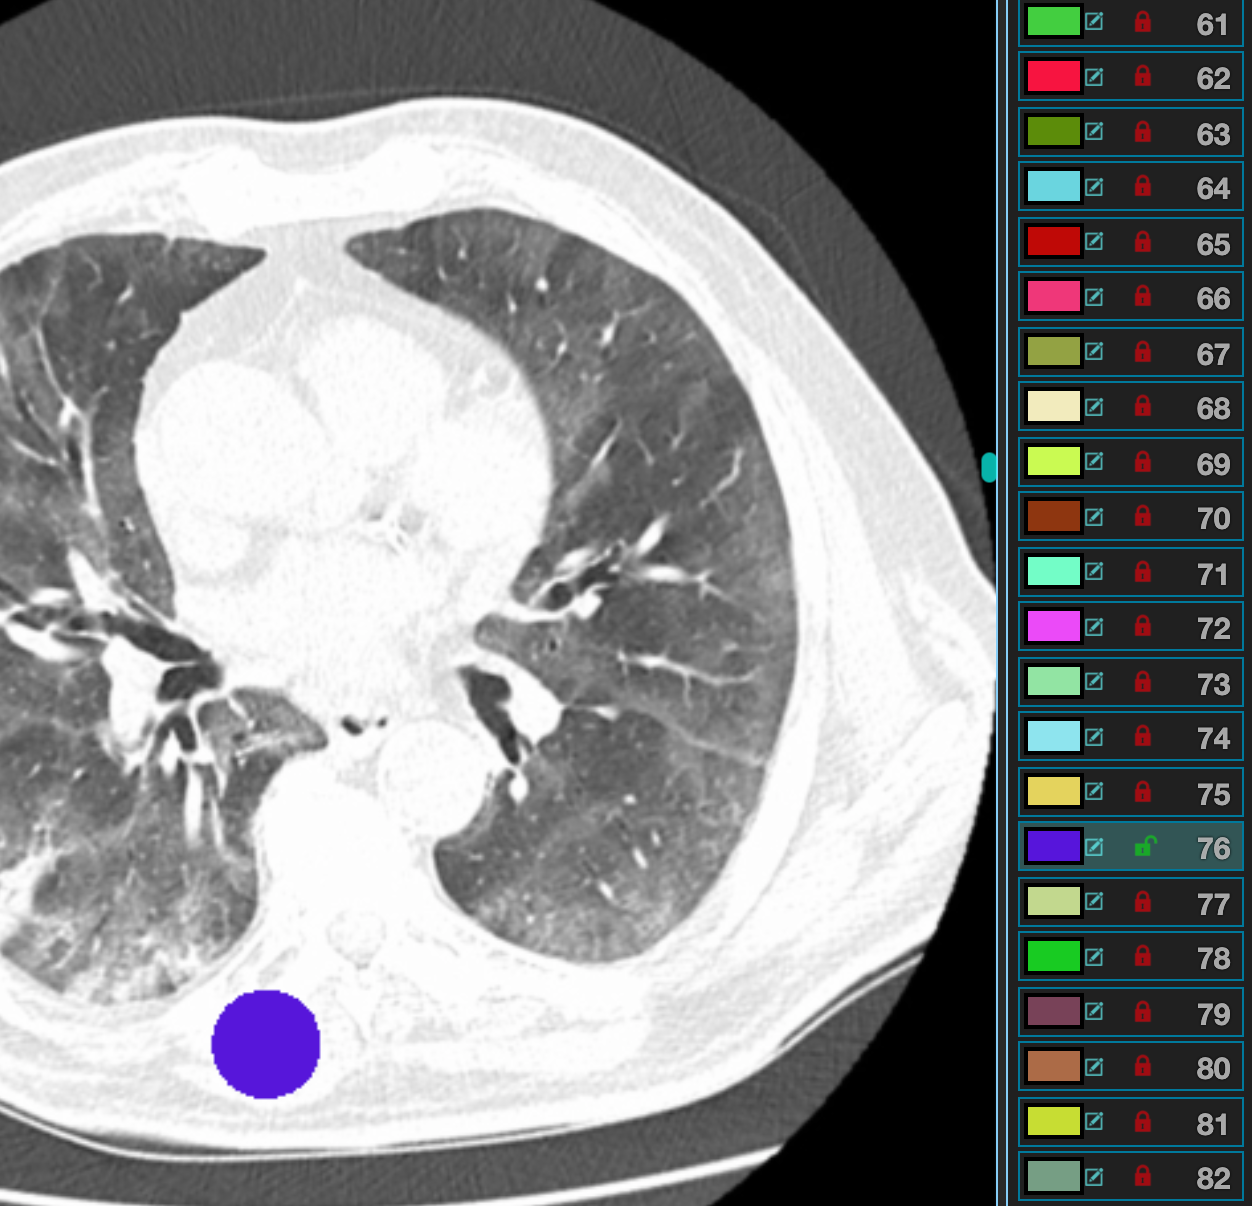

Medseg Free Medical Segmentation Online